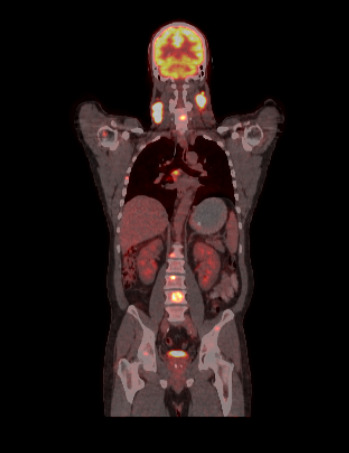

In solid tumors, hypereosinophilia is a rare phenomenon and is mainly associated with mucin-secreting carcinomas. Thyroid tumors associated with neutrophilia and/or eosinophilia have been described exclusively in patients with anaplastic thyroid cancer. Eosinophilia associated with papillary thyroid cancer is extremely rare and there are very few cases currently described. It has been suggested that three cytokines, namely interleukin-3 (IL-3), interleukin-5 (IL-5), and granulocyte-macrophage colony-stimulating factor (GM-CSF), may act as a peptide potential eosinophilic. To date, only three patients with differentiated thyroid cancer associated with eosinophilia have been reported, two of the papillary type and one of the medullary type. A 48-year-old patient consulted in 2022 due to bilateral cervical lymphadenopathy of 3 years' duration associated with wasting syndrome and hypereosinophilia. PET CT was requested, which showed hypermetabolic focus in the right thyroid lobe and lymph node, lung, bone, and liver metastases; Thyroid ultrasound showing a nodule of high suspicion of malignancy and a conglomerate of lymphadenopathy in the right lobe with positive needle wash for thyroglobulin. Hypereosinophilia was evaluated with initial leukocytosis values of GB 30,310/mm3 (10,608/mm3 of eosinophils) to maximum values of GB 77,090/mm3 (eosinophils 20,814/mm3). It was interpreted as paraneoplastic syndrome and corticosteroid therapy was started at immunosuppressive doses without response. Our observations presented in this article are in line with most studies reflecting that paraneoplastic hypereosinophilia is characterized by more advanced disease and poor prognosis.